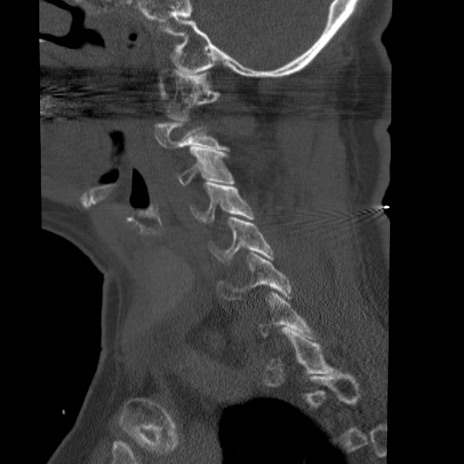

症例50 頚椎CT(矢状断像)

【症例】60歳代女性

【主訴】後頭部〜右後頸部にかけての痛み

【現病歴】本日飲食店でコーヒーを飲んでいたところ、突然後頭部〜右後頸部にかけて痛みが出現し、右上肢の感覚障害を伴ったため救急要請。

【身体所見】脳神経学的に明らかな異常所見を認めず。右上肢に軽度の感覚障害あり。

異常所見と診断は?